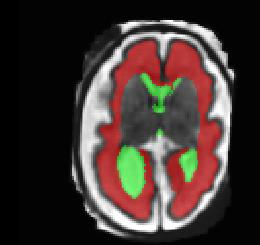

Limiting failures of machine learning systems is of paramount importance for safety-critical applications. In order to improve the robustness of machine learning systems, Distributionally Robust Optimization (DRO) has been proposed as a generalization of Empirical Risk Minimization (ERM). However, its use in deep learning has been severely restricted due to the relative inefficiency of the optimizers available for DRO in comparison to the wide-spread variants of Stochastic Gradient Descent (SGD) optimizers for ERM. We propose SGD with hardness weighted sampling, a principled and efficient optimization method for DRO in machine learning that is particularly suited in the context of deep learning. Similar to a hard example mining strategy in practice, the proposed algorithm is straightforward to implement and computationally as efficient as SGD-based optimizers used for deep learning, requiring minimal overhead computation. In contrast to typical ad hoc hard mining approaches, we prove the convergence of our DRO algorithm for over-parameterized deep learning networks with ReLU activation and a finite number of layers and parameters. Our experiments on fetal brain 3D MRI segmentation and brain tumor segmentation in MRI demonstrate the feasibility and the usefulness of our approach. Using our hardness weighted sampling for training a state-of-the-art deep learning pipeline leads to improved robustness to anatomical variabilities in automatic fetal brain 3D MRI segmentation using deep learning and to improved robustness to the image protocol variations in brain tumor segmentation. Our code is available at https://github.com/LucasFidon/HardnessWeightedSampler.